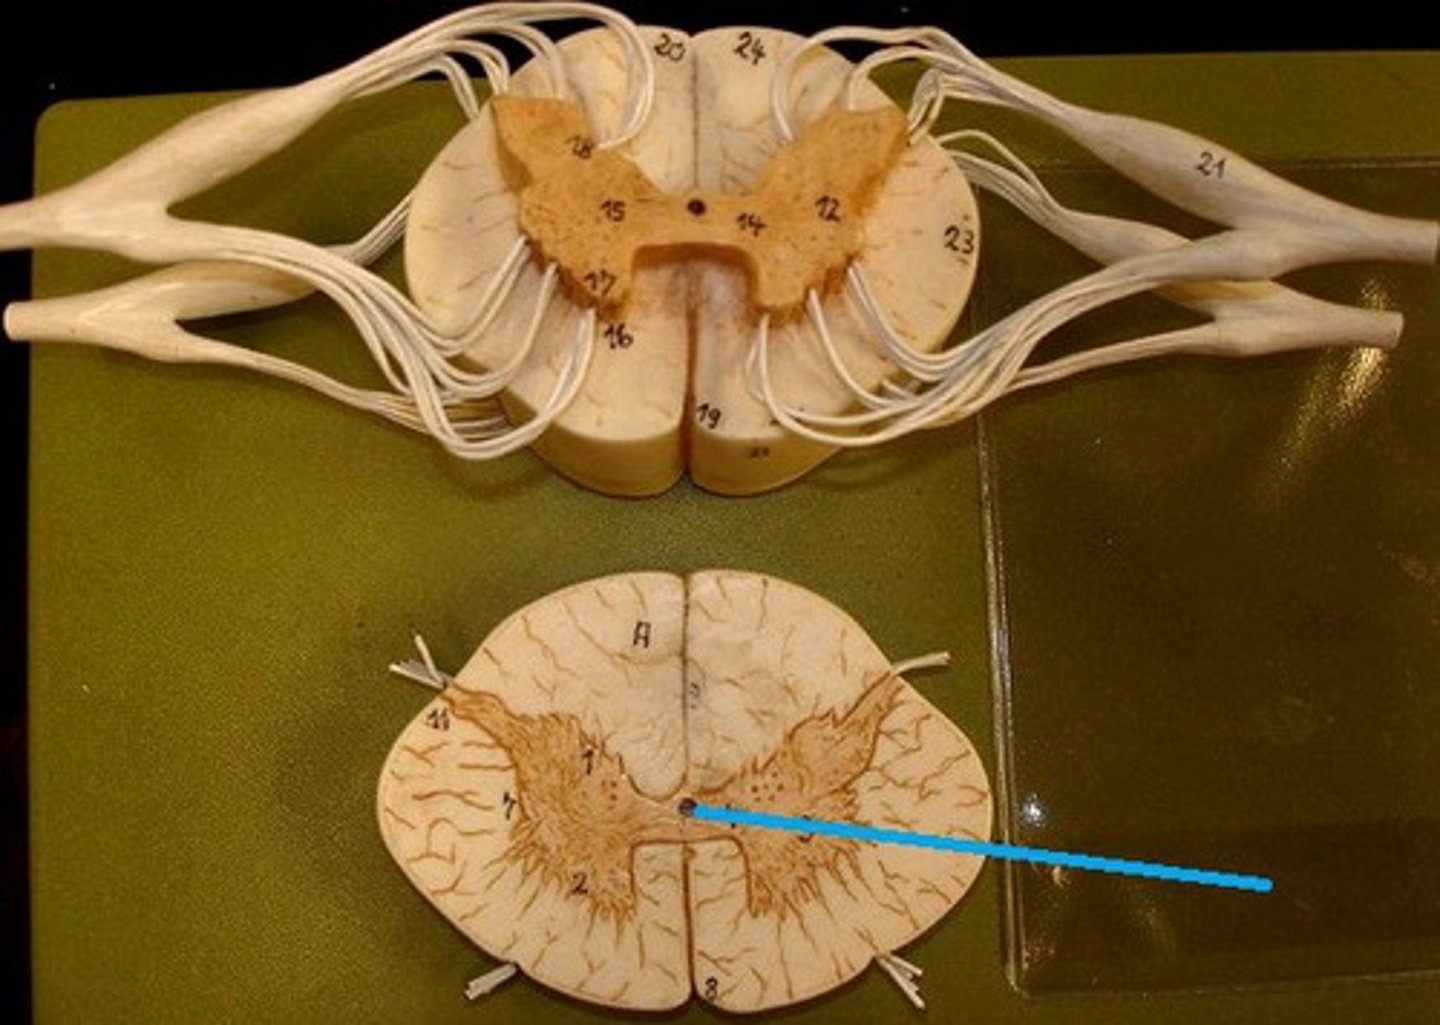

spinal cord

a major part of the central nervous system which conducts sensory and motor nerve impulses to and from the brain; housed within the vertebral canal

central canal of spinal cord

center of spinal cord which contains cerebrospinal fluid

posterior median sulcus

a shallow vertical groove dividing the spinal cord throughout its whole length in the midline posteriorly.

anterior median fissure

a groove along the anterior midline of the spinal cord that incompletely divides it into symmetrical halves

gray matter of the spinal cord

cell bodies, dendrites, and unmyelinated axons arranges in a butterfly shape with anterior and posterior "horns"

posterior (dorsal) horns

contain axons of sensory neurons and cell bodies (sensory nuclei) of interneurons

31 pairs of nerves arising from the spinal cord; letter abbreviation for region of spine they originate from; forms where the anterior and posterior roots join; mixed nerves (contain sensory and motor fibers)

posterior (dorsal) rootlets

merge to form a root

posterior (dorsal) root

contains sensory axons

posterior (dorsal) root ganglion

contains cell bodies of sensory neurons

true spinal nerve

anterior root

contains motor axons